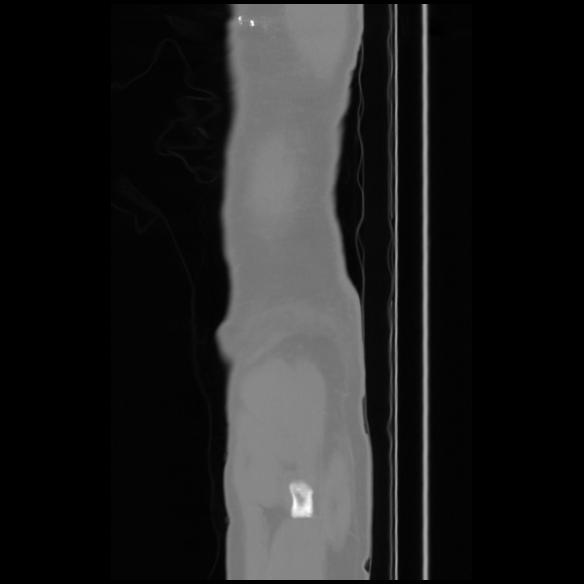

7 CUERPO,CE,Sagittal,3.000,CUERPO,Sagittal,